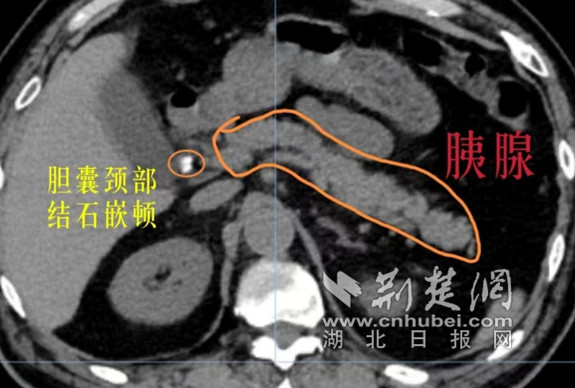

医生们立即为关爹爹进行了相关检查,然而急查腹部CT提示关爹爹的胆总管下段结石、胆囊结石伴慢性胆囊炎急性发作、急性胰腺炎伴有梗阻性黄疸,属于典型的“排石”现象。随后,又接到了检验科的危急值报告,报告显示关爹爹的淀粉酶高至3829U/L(正常值:35-135U/L),提示其为急性胆源性胰腺炎,且总胆红素指标也高至102.3umol/L(正常值:0-26umol/L)。

“‘排石’现象是指胆囊里的石头排到了胆总管里,而这也是引起梗阻性黄疸和急性胰腺炎的主要原因。胆囊管正常的直径是2-3毫米,而关爹爹的多发结石直径也都在3毫米左右,所以小结石极其容易随着胆囊收缩排入胆总管。”王君璞医生解释道,“再加上此次急性胰腺炎发作,腹部剧烈的疼痛让爹爹无法进食且伴有恶心呕吐,蛋白降低,引起腹腔积液、胸腔积液和肺部感染;同时刺激膈肌,从而引起肺不张,每一次呼吸都伴随着疼痛。如不赶快进行手术,关爹爹随时面临着休克性死亡。”